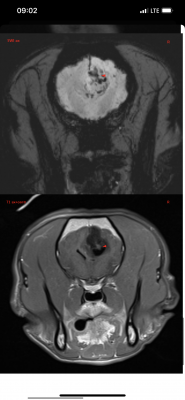

Вчера делали Марику МРТ в клинике Skolkovo Vet, если кому-то интересно, стоит чуть больше 12000₽. Результат неутешительный. Заключение:

МР-признаки новообразования в области лобной и теменной долей коры больших полушарий головного мозга справа, с очагами кровоизлияния и перифокальным отеком.

МР-признаки постсудорожных изменений.

Опухоль у моего мальчика(( она и вызывает судороги. Написала сегодня в вотс ап Хохлову, не знаю ответит ли, готова ехать к нему в клинику если он вообще принимает пациентов. К Дубовицкой попасть нереально, там очередь минимум на 1,5 месяца, есть онлайн консультация, стоит как и очный прием 7000₽, но ее рекомендуют скорее как второе мнение после очного осмотра у невролога. Рекомендовали еще Субботина из Белого Клыка, но увы, он по известным всем причинам с 2022 работает в вет клинике в Грузии. Продолжаю давать Кеппру и Габапентин